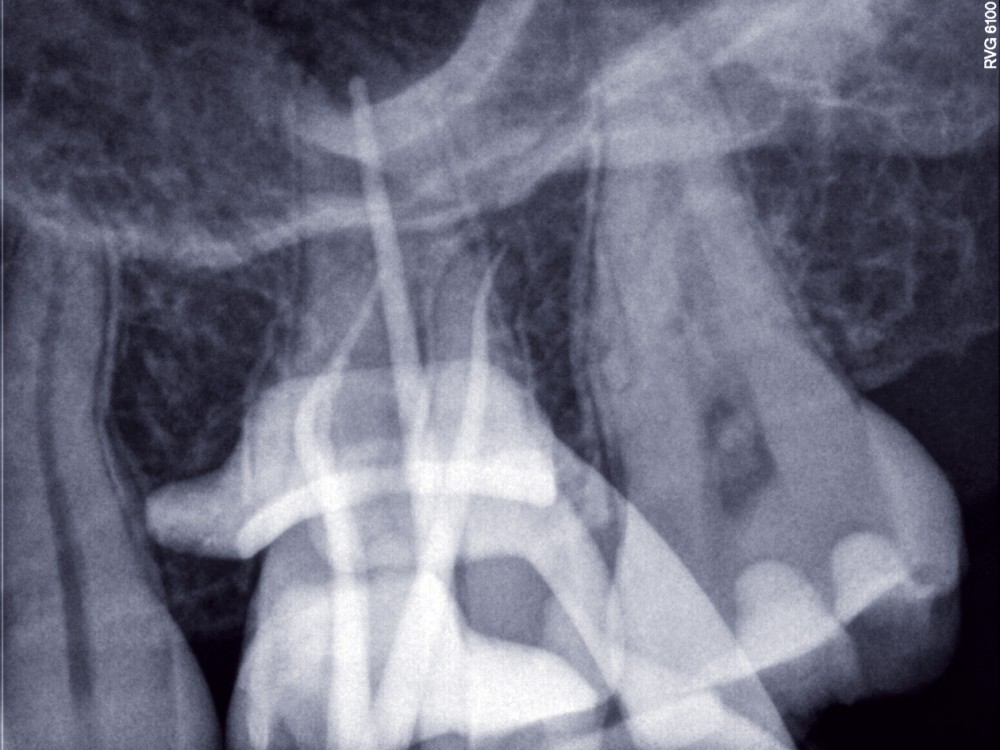

Traitement endodontique d’une première molaire maxillaire

L’endodontie a connu de formidables bouleversements techniques au cours de ces dernières années, soit par l’amélioration et l’intégration de technologies déjà connues, soit par l’introduction de techniques, de matériaux et de matériels innovants.Le but de cet article est de décrire la mise en application des matériaux et techniques dans le cadre d’un protocole précis qui guide le praticien pas-à-pas à travers les différentes étapes du traitement d’une molaire maxillaire, depuis le diagnostic et la pose de la digue jusqu’à l’étape finale de l’obturation canalaire, en passant par la recherche des canaux et la mise en forme avec les systèmes les plus récents.Ce protocole qui met les évolutions techniques au service des principes de base de l’endodontie, permet de traiter la majorité des cas cliniques de manière fiable et reproductible en omnipratique.